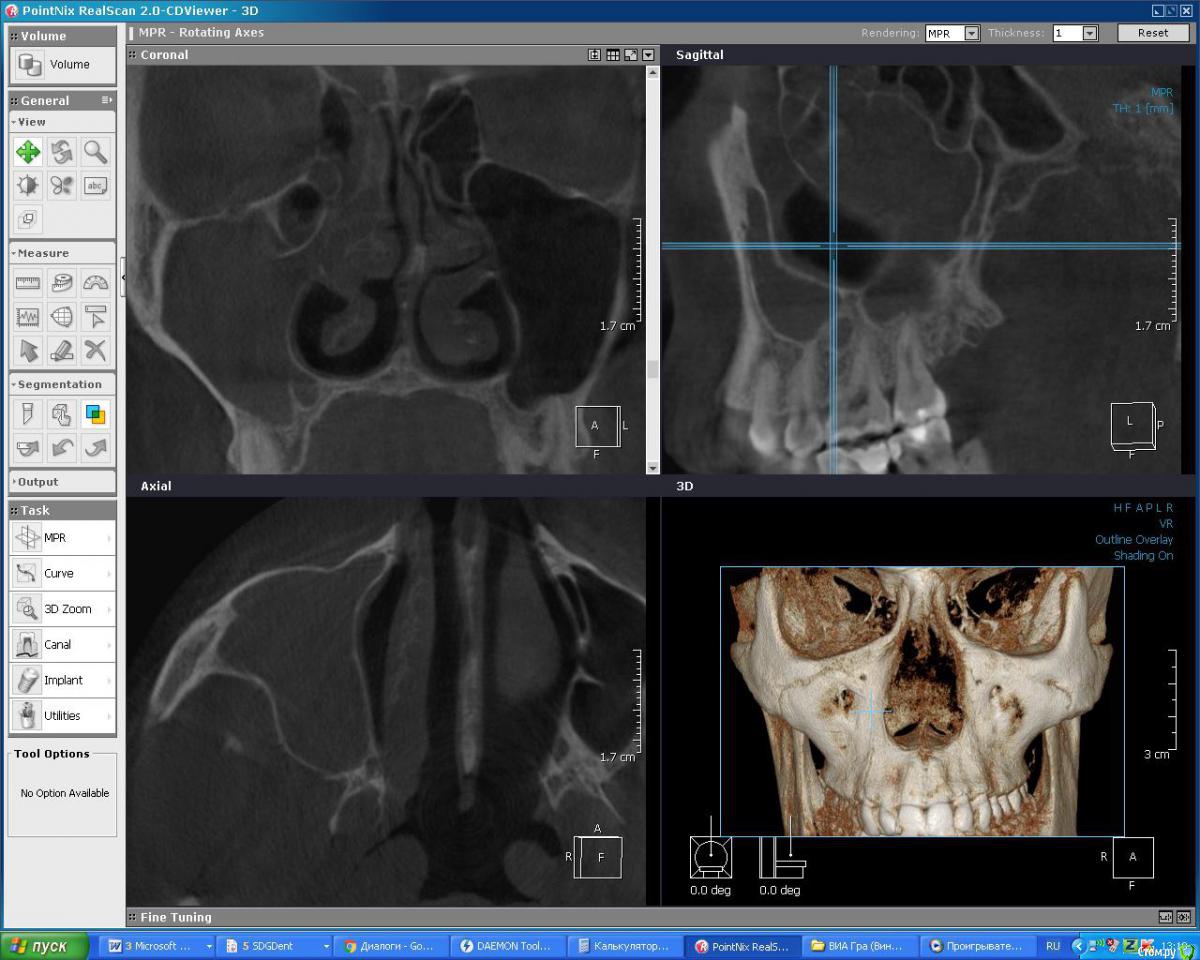

DoktorDre Опубликовано 6 декабря, 2015 Поделиться Опубликовано 6 декабря, 2015 Всем доброго времени суток! Ситуация - 10 дней назад удалил 1.8 не сильно кариозный. Соустья вроде не было. Но шнайдерову видел. Зашил. Через неделю - лунка пустая, отделяемого нет. Но есть лёгкий альвеолит.промыл,хг и в лунку метрогил.на след день все прошло.сегодня боли, голова болит, субфибрильная. Направил на кт. Вот оно.Чтото у меня ни разу такого не было, жидкости я не вижу в пазухе.назначил зифактор 500.что делать то? Ждать, пункция? к3.bmp Ссылка на комментарий

Евгений Ходыкин Опубликовано 6 декабря, 2015 Поделиться Опубликовано 6 декабря, 2015 По кт сообщение то видно?? Тоже кажется, что 1.8 не при делах... 2 Ссылка на комментарий